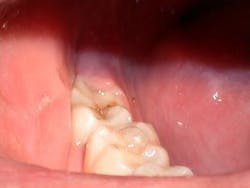

In this case, due to an apprehensive patient, a few drops of 4% Citanest, with the aid of the Wand®, were delivered into the operculum. The tissue was removed with the 980nm diode laser, using the High Fluence Technique developed by the author (Fig. 2). The technique uses higher powers in a gated pulsed mode with water for cooling to accomplish ablation of the tissue at a rapid pace. An excessive time of exposure is often more damaging than the total power delivered, as excessive time allows for conduction of residual energy into the adjacent tissues causing collateral damage and thus postoperative pain. Fifteen watts of power was used gated .05 seconds on and .05 seconds off a 400um fiber and 15 seconds of laser time with water for cooling provided char-free, bloodless ablation. The author believes that this technique is not contrary to the Academy of Laser Dentistry's credo of "using the lowest power to get the job done," but rather it is consistent with it with one addition, "completing treatment in the shortest time while remaining in control." Excessive time can be our enemy when cutting tissue. The author also cautions that the higher fluences and water-cooling he advocates are only to be used with the 980nm wavelength and after proper training in the technique (Fig. 2).